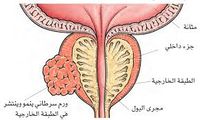

سرطان الپروستاتا

مقالة مفصلة: سرطان الپروستاتا

مقالة مفصلة: سرطان الپروستاتا

| سرطان الپروستاتا | ||

| معدل الانتشار | 1.1 مليون حالة جديدة (2014)[3] | |

| معدل البقاء 5 سنوات | 99% (الولايات المتحدة)[4] | |

| حالات الوفاة | 307.000 (2014)[3] | |

| عوامل الخطورة | تقدم العمر؛ وربما يكون للغذاء الغني بالدهون دور. يميل سرطان الپروستاتا إلى أن يحدث في أسر معينة، ولكن ليس واضحاً ما إذا كان السبب جينياً (وراثياً) أو بيئياً. إن معدل إصابة الرجال السود يزيد على البيض بنسبة 37%، كما أن معدل الوفيات عند السود ضعفه عند البيض. | |

| العلامات المنذرة | ضَعْف تدفق البول، تقطع التبول أو صعوبة التحكم فيه؛ ازدياد الحاجة إلى التبول؛ تبول مؤلم؛ ألم في الحوض أو الظهر. | |

| الكشف والتشخيص | يجب إجراء فحص بالإصبع من المستقيم digital rectal examination سنوياً لكل رجل تجاوز الخمسين. ويمكن لفحص الدم، للكشف عن المستضد النوعي للپروستاتا prostate-specific antigen (PSA)، أن يشير إلى وجود شذوذات في الپروستاتا في مرحلتها المبكرة. كما يمكن عن طريق الفحص بالموجات فوق الصوتية عبر المستقيم transrectal ultrasound تأكيد النتائج المشتبه بها في فحوص أخرى. ويشير فحص كمية الدنا DNA في الخلايا الشاذة إلى مدى خباثة السرطان.

| |

| العلاج | تُعتبر إزالة الپروستاتا عملا روتينيا. كما تُستخدم المعالجة الشعاعية إما كبديل أو بالمشاركة مع استئصال الپروستاتا prostatectomy. وبالنسبة للنقائل الورمية تُعطى أدوية تستطيع أن تحول بين الخلايا الورمية وحصولها على الهرمونات الذكرية التي تحتاج إليها كي تنمو.

| |

| ملاحظات | سرطان الپروستاتا هو السبب الرئيسي الثاني للوفيات عند الرجال نتيجة للسرطان. | |